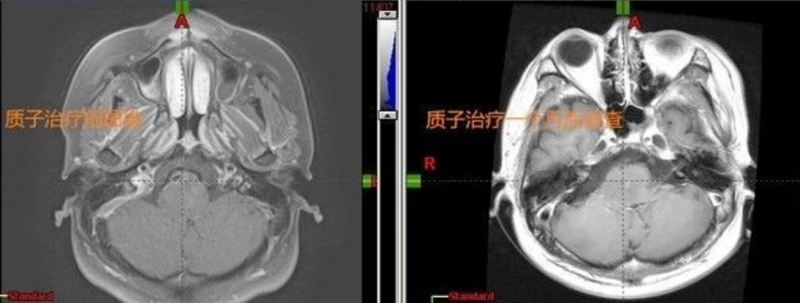

质子治疗前后对比:肿瘤得到明显控制,走路不稳,肢体无力,喝水呛咳等症状逐渐消失

治疗后九个月复查:肿瘤持续缩小,由治疗一个月横截面2.9cm×2.92cm缩小至现在的1.86cm×2.32cm